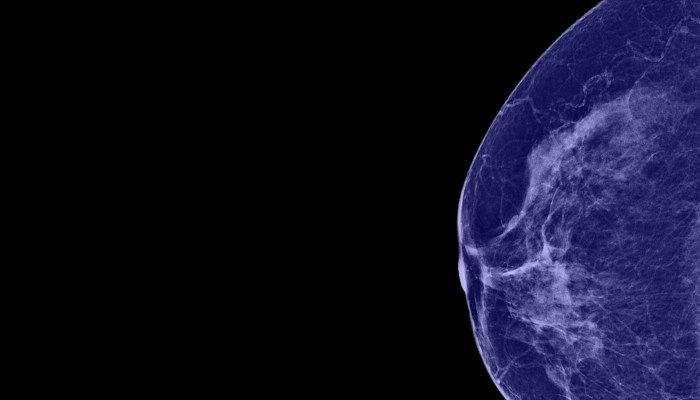

- Маммография. С помощью маммограммы специалист может объективно оценить состояние протоков, выявить наличие новообразований или подтвердить их отсутствие.